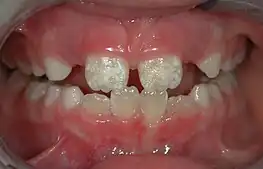

- Pediatric dentistry (also called pedodontics) – Dentistry for children